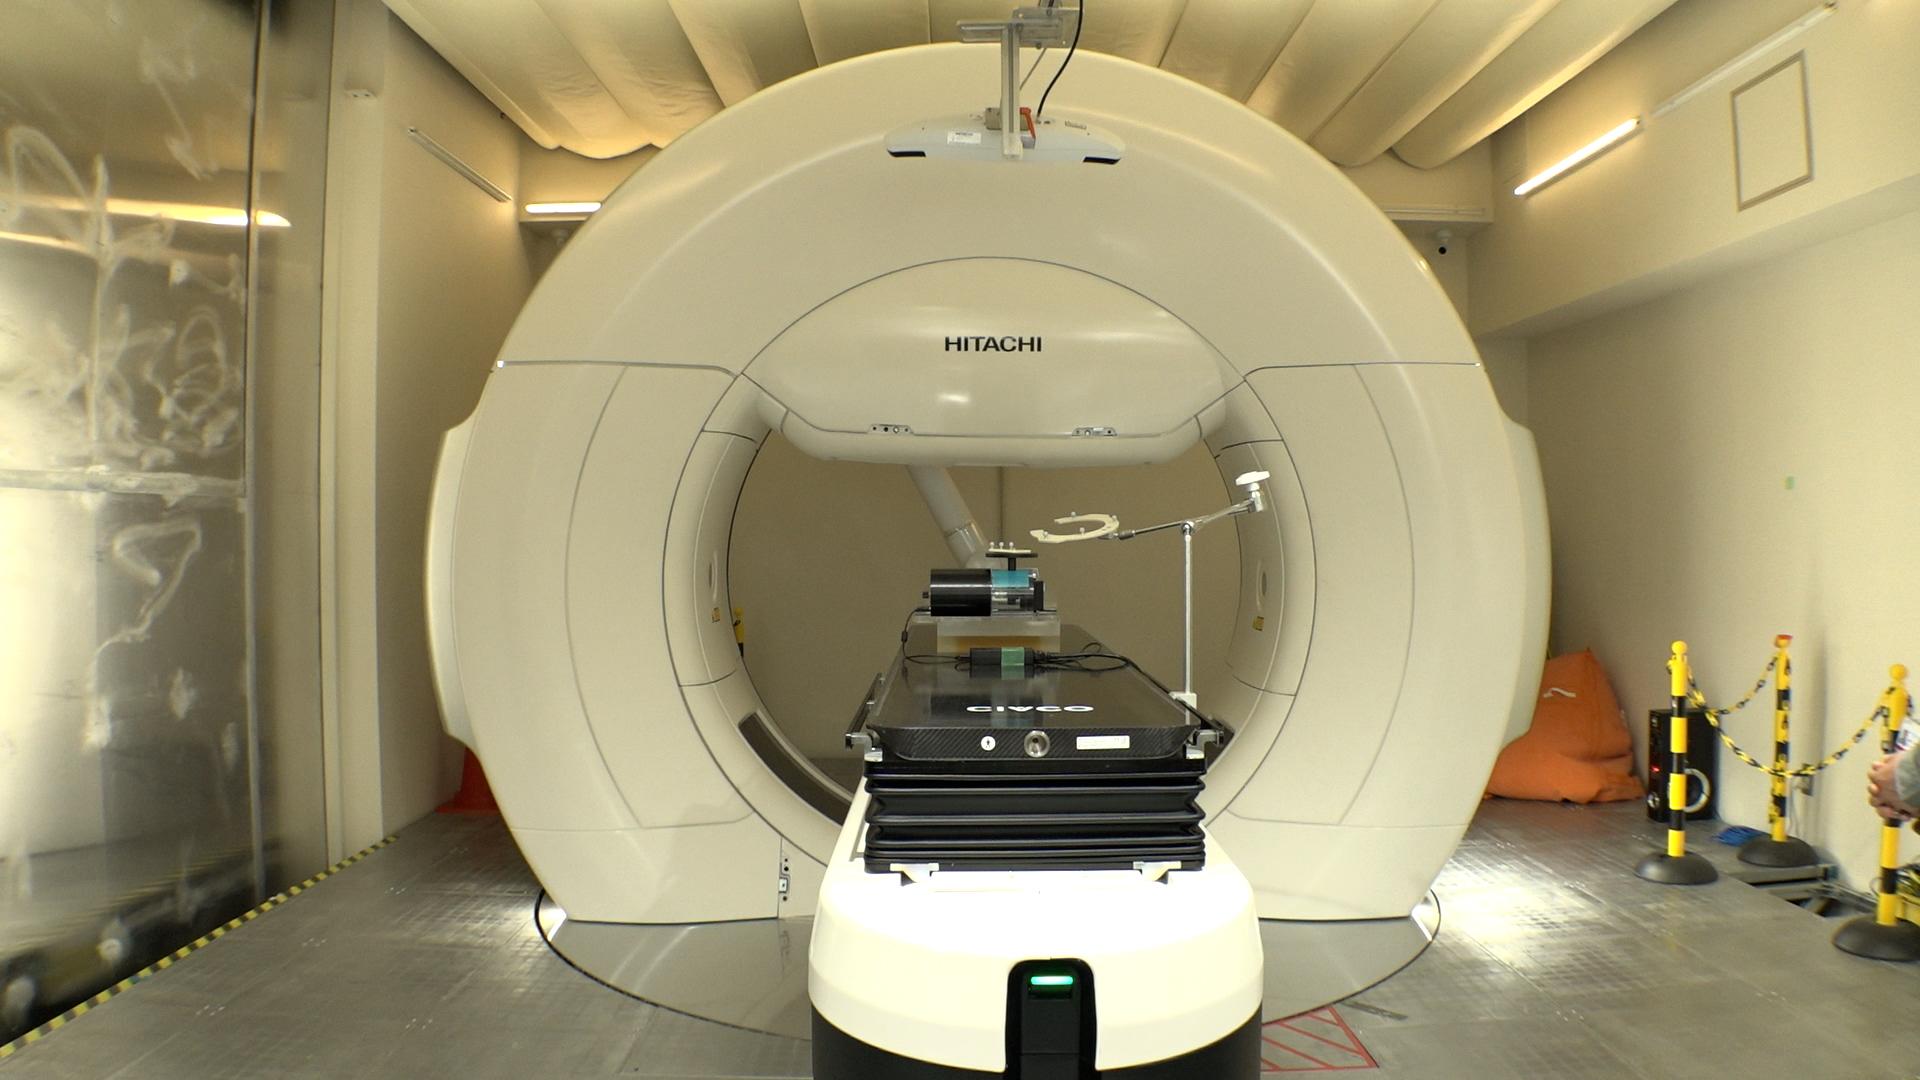

2人に1人が、癌になる時代。外科手術や薬物療法と並ぶ“癌治療の3本柱”の1つが、放射線治療だ。進化する癌の高精度放射線治療の最前線を取材。

2人に1人が、癌になる時代。外科手術や薬物療法と並ぶ“癌治療の3本柱”の1つが、放射線治療だ。「切らずに治せる治療」として身体への負担も少なく、仕事がある“現役世代”の患者が働きながら治療を受けられるメリットがあり、国内で新たに放射線治療を受ける癌患者は年間約23万人に増加している。

その放射線治療は、AIの進化などによる技術革新で、今後さらに治療の精度が上がることが期待されている。しかし、国内メーカーは装置の製造から相次ぎ撤退し、医療現場では海外メーカー製がシェアをほぼ独占する状態になっていた。ガイアは、進化する癌の高精度放射線治療の最前線を取材。これまでにない最新鋭の性能を武器に“悲願の国産装置”を開発した「日立ハイテク」と医師たちの挑戦を追う。